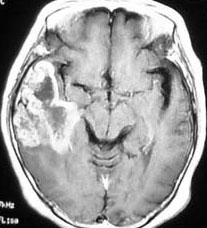

診断:MRIでの特徴

• 診断はMRI検査をします,それだけで十分です

• ガドリニウム造影剤で腫瘍の周辺が白く造影されます

• いびつな形になるのが特徴です

• しかし,ほんとうの腫瘍の広がりは,T2強調あるいはFLAIR(フレア)という画像で,白く滲むように写る部分すべてです

• 手術でガドリニウム増強される部分が全部取れると,お医者さんは全摘出できたといいますが,それは間違いです

• FLAIR画像で白く見える部分が全て取れてはじめて,画像上での全摘出と言えます

• それでもなお,隠れた腫瘍細胞は周囲に滲み込んで残っています

典型的な膠芽腫のガドリニウム増強画像です。右の側頭葉から発生したために目立った症状が無く,この大きさで発症しました。何となくボッとしていると言うのが訴えでした。腫瘍の周囲がガドリニウムで白く増強されて,内部は壊死で低信号(黒っぽい)になっています。

左がガドリニウム増強像で,手術ではこの部分が取れれば全摘出といわれるのですが,実際は右側のフレア画像で白っぽく見える所には腫瘍が滲み込んでいます。この部分を全て摘出してはじめて,画像上の全摘出といいます。全摘出は無理でしょう